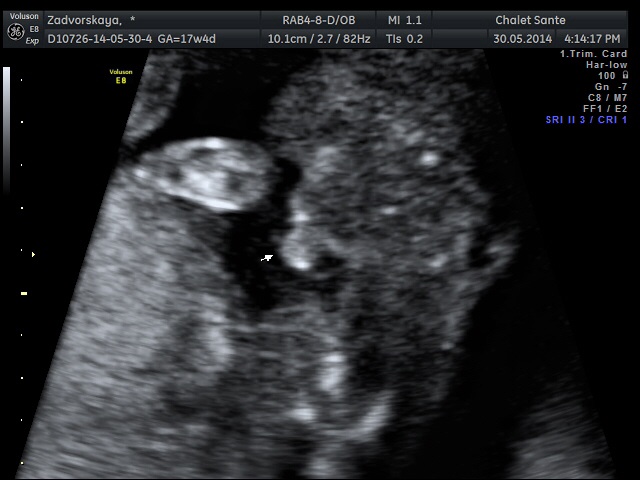

У нас сынок)))

Вопросы про УЗИ, обследования и анализы: что, где, как, когда?Девочки гляньте, это же мальчик??))) врач говорит 100% мальчуган, муж поверить не может своему счастью!!!))))

Стрелочки указывают на писюн))) нам все показали и рассказали, про все все органы и части тела, я оч довольна, бесплатное узи это конечно для врачей больше информация, а тут все рассказывают, показывают)))) нам оч понравилось)